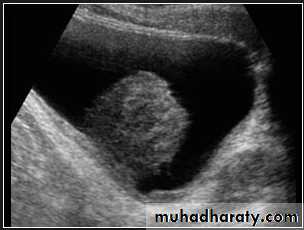

Renal ultrasound is a simple noninvasive examination .The kidney is bean shaped and has bright central echoes because of the fat surrounding the collecting system.

Normal renal ultrasound.

A longitudinal view of the right kidney was obtained by passing the sound beam through the right lobe of the liver. The kidney is seen behind this, outlined by the markers. The central bright echoes in the kidney are due to fat around the collecting system.